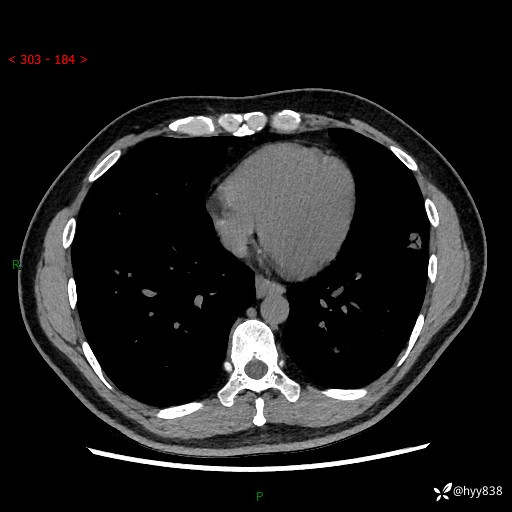

中年男性,胸闷3月余。多发团片、肺小叶分布、空气支气管征、明显强化---结果公布~

现病史:患者3月前出现胸闷,卧位时加重,坐位时缓解,无咽痛、咳嗽,无头痛,无全身酸痛,无结膜充血,无胸痛、心慌,无咯血,无呼吸困难,无咳痰,2024-07-02于当地市第一民医院行胸部CT,结果不详,2024-07-05就诊于我院急诊内科,行胸部CT同时增强,结果示:左肺下叶多发结节灶,考虑感染可能。今患者为求进一步诊治来我院,门诊以“肺部感染”收入我科。 患者本次起病来精神、食欲、睡眠尚可,大小便可,体力,体重无明显变化。

胸部CT平扫+增强

各期CT值:30hu 90hu 77hu